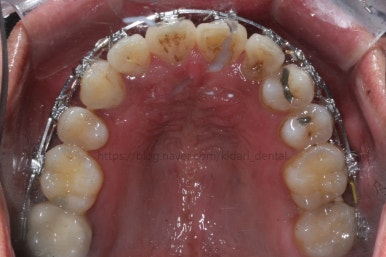

부산치아교정 키다리아저씨치과에 처음 내원 당시의 입안 모습입니다.

여러 가지 문제점이 있는데 하나씩 살펴볼게요.

화살표 부분에 원래 송곳니가 있어야 되는데 보이질 않네요. 결손치아일 수도 있고 매복치아일 수도 있겠어요.

왼쪽 위 어금니도 한 개가 없어서 빈공간이 약간 남아있어요.

파노라마 X-ray 사진 입니다.

사랑니가 굉장히 위쪽으로 묻혀 있어요. 이렇게 묻혀 있는 사랑니는 사실상 그냥 놔둬도 괜찮아요.

과잉치가 보이네요. 앞니 사이에 과잉치는 굉장히 빈번한데 주위 치아에 안좋은 영향을 줄 때는 뽑는게 좋아요. 이번 환자분은 뽑기로 했어요.

입 안에서 보이지 않던 송곳니가 여기 있었네요. 송곳니는 굉장히 중요한 치아라서 왠만하면 살려 쓰는게 가장 좋긴한데요. 위치랑 다른치아와의 관계 등을 고려해서 뽑을지, 꺼내쓸 지를 결정해야 돼요.